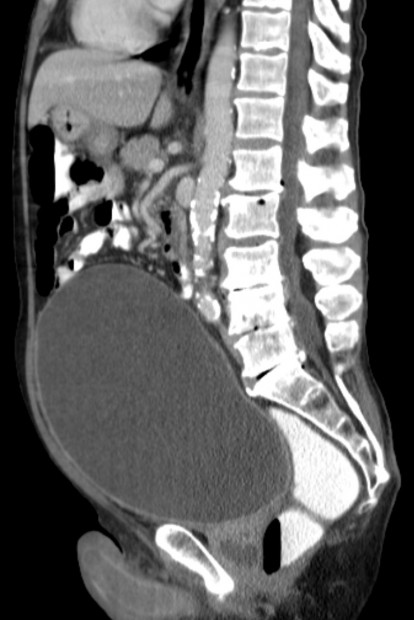

- Retence moči je definováno jako zadržení moči v močovém měchýři.

Zdroj: Autor Hellerhoff, Harnverhalt mit riesiger Blase in der Computertomographie., licence Creative Commons BY-SA 3.0.

Obr. 15. Retence moči